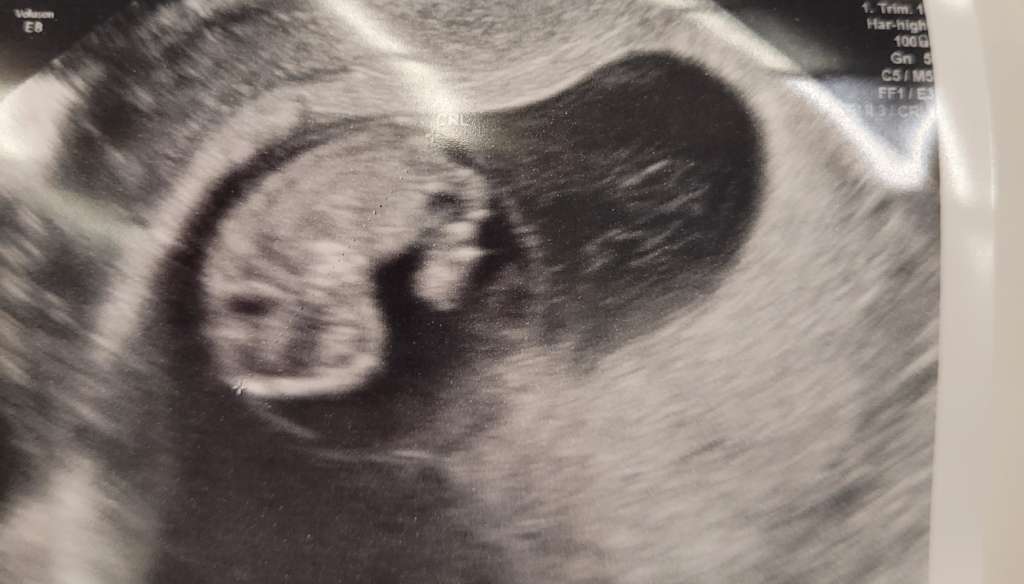

Mamy się cudownie 😍😍😍

Załączniki

• a317241e-2e13-4c0b-a1a4-3307cde52d48.jpeg

a317241e-2e13-4c0b-a1a4-3307cde52d48.jpeg

38,3 KB · Wyświetleń: 145